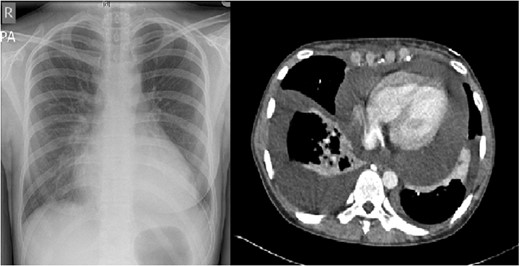

Pre-operative chest radiograph and axial view of a CT thorax, demonstrating a large pericardial collection.